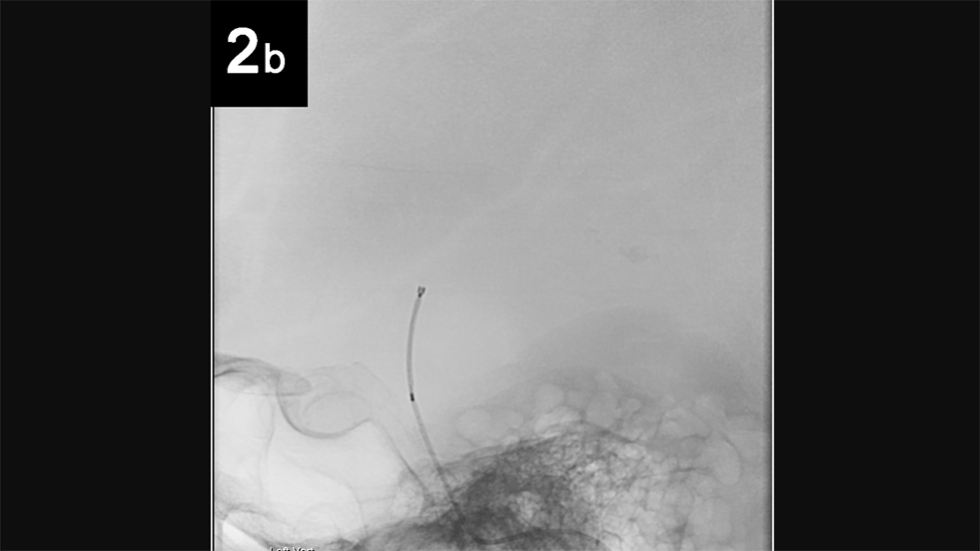

Intrasaccular: 2b

5 of 6